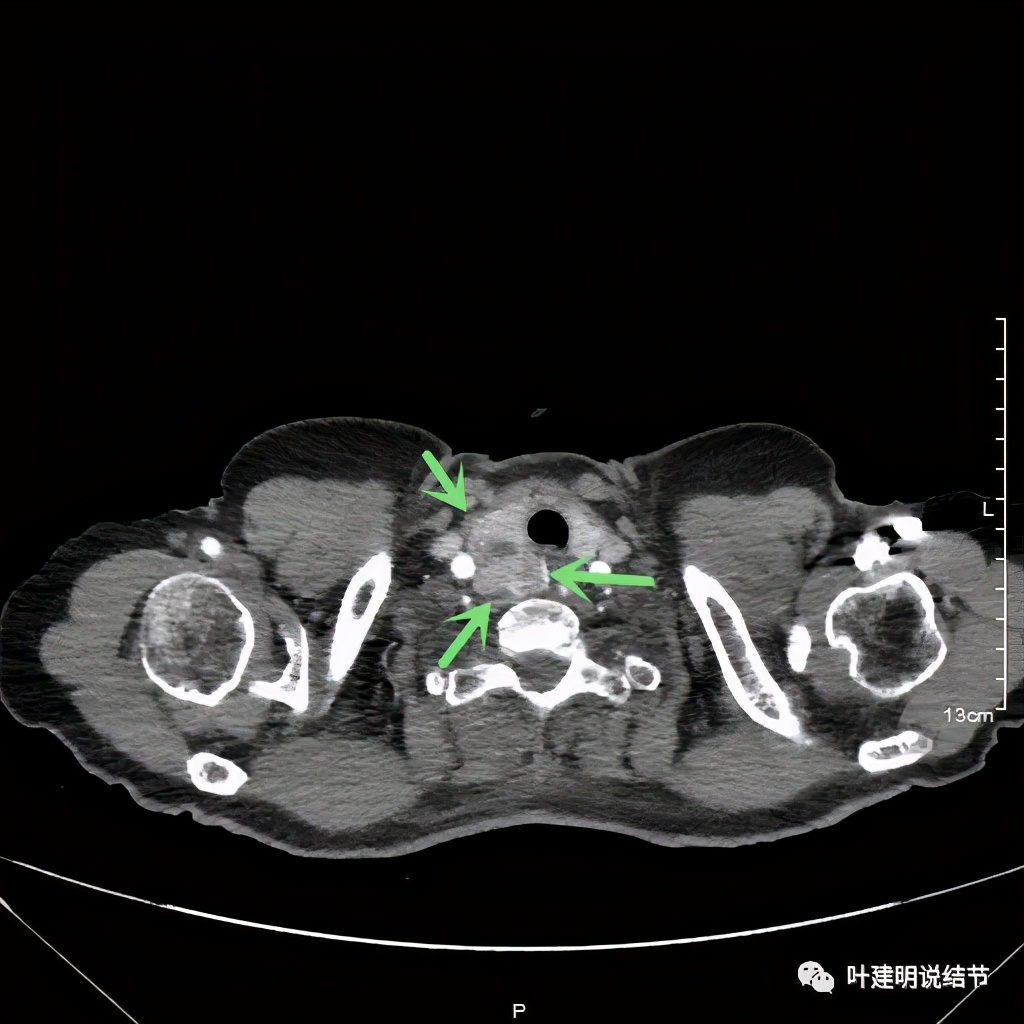

上图红色示肿瘤,粉色示肿瘤与气管关系密切,而且肿瘤密度不均杂乱

上图红色示肿瘤,黄色示气管,粉色示肿瘤与气管关系密切,而且肿瘤密度不均杂乱

上图红色示肿瘤,黄色示气管,粉色示肿瘤与气管关系密切,桔色示左无名静脉,蓝色示上腔静脉,而且肿瘤密度不均杂乱